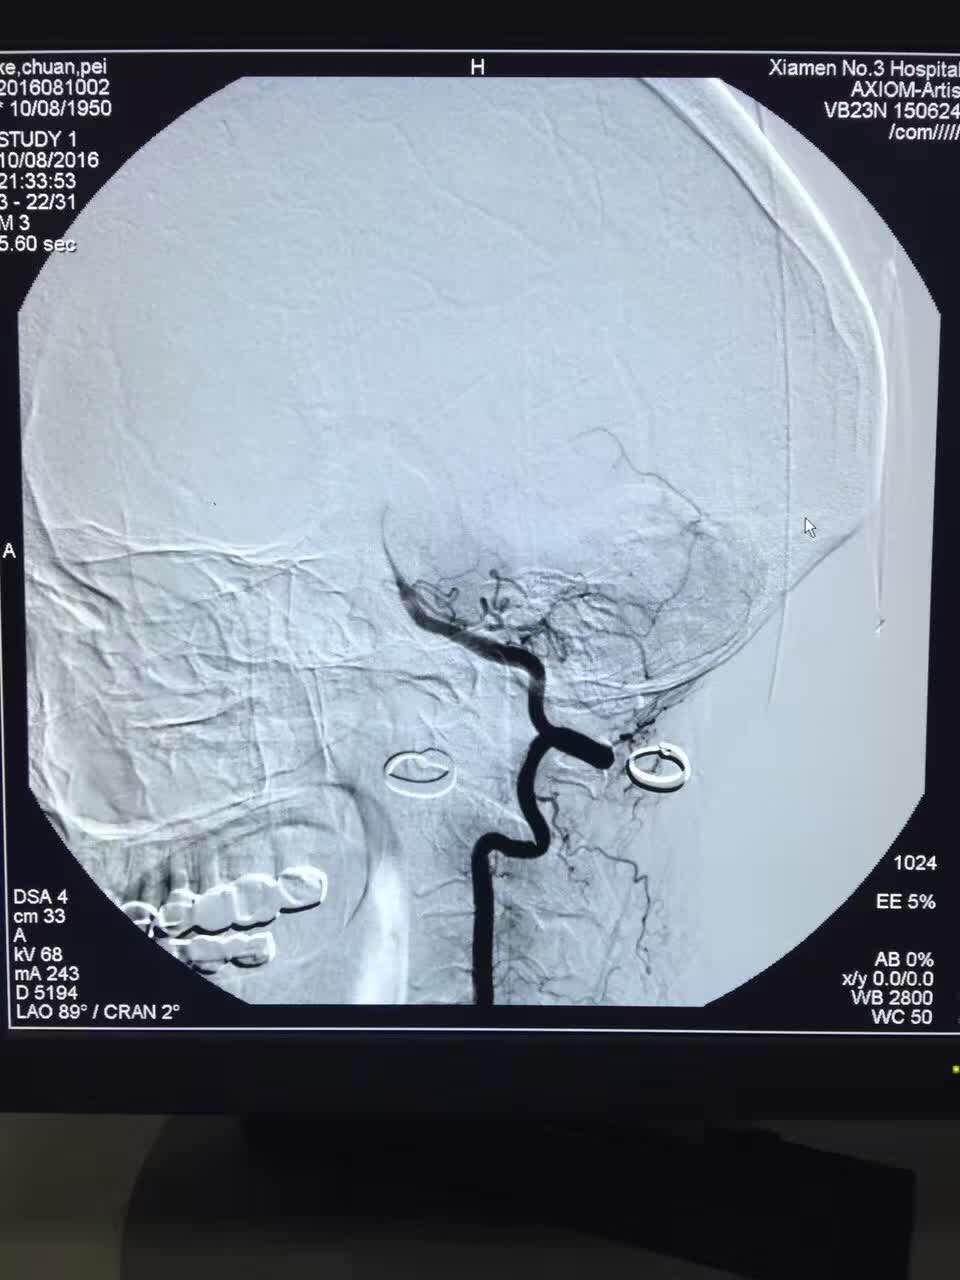

第三医院接诊后,经体检及急诊CT检查,诊断患者为严重的脑卒中(脑血管堵塞)。24小时待命的脑卒中治疗团队立即到院接诊病人。神经内科许文勇团队评估后,立即给予药物溶栓治疗,但药物完全进入体内后,观察半个小时,陈女士右侧肢体肢力仍无明显好转,表明血管堵塞严重,药物已无法溶解疏通。如果在治疗时间窗(8小时)内血管无法打通,病人将产生极为严重的后果。此时的关键是尽快打通堵塞的血管,必须采用高新技术动脉介入取栓方能解决。为此,神经外科陈金龙团队迅速将病人转入导管室进行脑血管造影,确定脑堵塞的部位,发现陈女士为颅内左侧大脑中动脉完全闭塞,即予以动脉介入取栓,介入医生将一个微导管和微导丝反伸入患者的右侧股动脉,反复“疏通”闭塞部位,用球囊在血管狭窄处扩张成形后置入支架。微导管前端有一个可以开合的“网兜”,当微导管伸至血栓处时,打开“网兜”。此时血栓就会附着在网兜上。把微导管往回拉,血栓就被拉出血管。介入医生连续“撒网”数次,取出长度约2厘米的血栓。当天夜里,陈女士的右侧肢体肌力完全恢复,在及时有效的治疗下,术后恢复状况良好,没有留下任何后遗症。